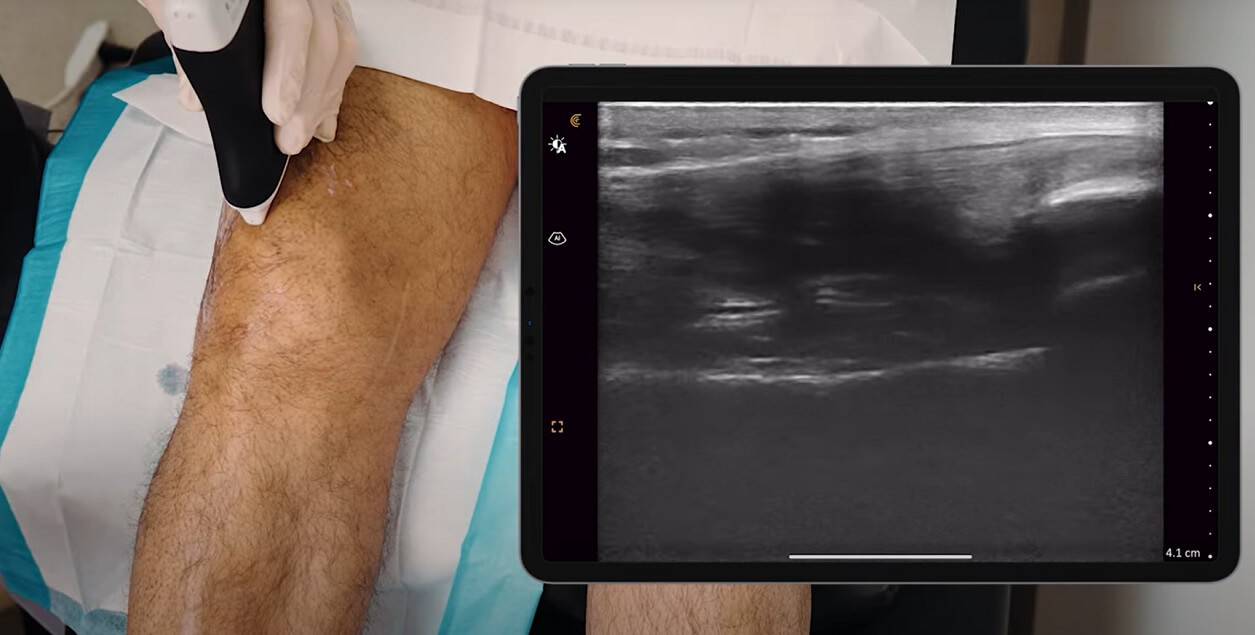

Ovaj pregled se izvodi pomoću posebnog uređaja koji se naziva transduktor (ultrazvučna sonda), koji šalje ultrazvučne talase unutar mekih tkiva kolena.

Ovi talasi se odbijaju (ultrazvučni “eho”) od različitih struktura – kao što su mišići, tetive, ligamenti i tečnosti – i zatim se pretvaraju u slike na ekranu računara u realnom vremenu.

Istovremeno, lekar gleda i prati na ekranu računara unutrašnje strukture kolena u realnom vremenu.

Ove slike se formirau na osnovu ultrazvučnih talasa koji se šalju u unutrašnje strukture kolena. Zatim, ovi talasi se odbijaju od tih struktura, što se na monitoru računara prikazuje kao slika.